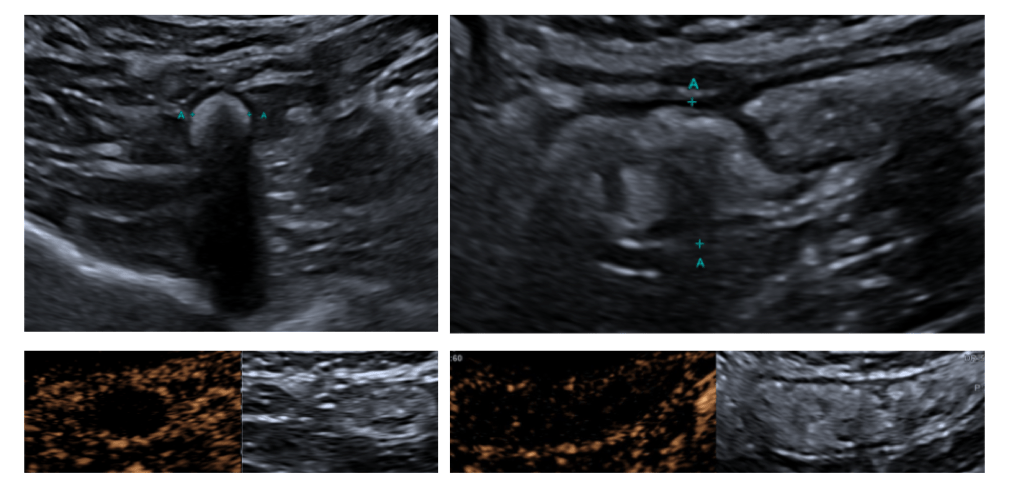

B-mode ultrasound and Contrast-enhanced ultrasound (CEUS)

An enlarged appendix is identified, measuring 15 mm in diameter and 4.8 cm in length, with a distal appendicolith measuring 8 mm (yellow arrow). After IV contrast administration, there is mural enhancement (2 mm) (Blue arrow) with no intraluminal contrast opacification. These findings suggest an appendiceal mucocele (mucinous neoplasm). No signs of complication are observed. (Fig. 1)